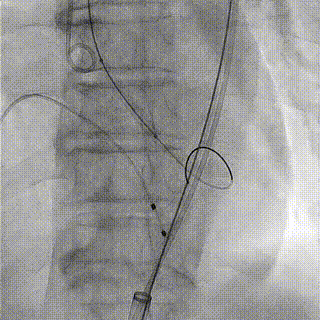

患者手术过程顺利,予球囊预扩后,由于瓣膜反流加重患者血压迅速降低,凭借过硬的高超技术与紧密的团队合作,王焱教授团队对他立即经右股动脉植入人工瓣膜一枚,血压即刻回升,行造影及超声评估提示人工主动脉瓣瓣膜植入效果良好,二尖瓣中度返流即刻减轻为轻度。术后TTE显示:主动脉瓣无瓣周反流,PGmean:18mmHg,Vmax:2.1m/s 经导管测量PGmean:7mmHg。患者术后恢复顺利,无心脏及血管并发症。